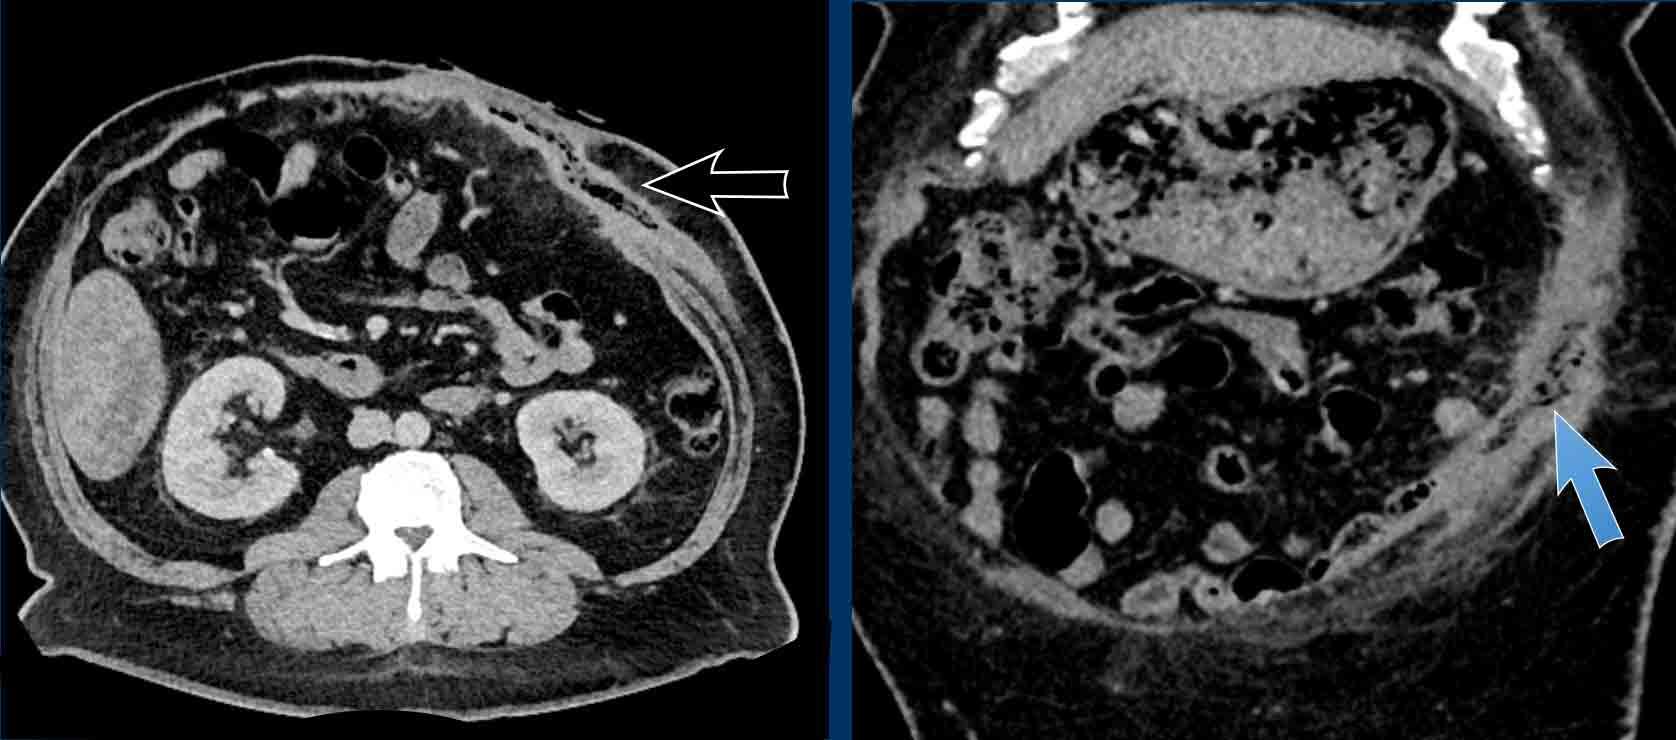

Ở bệnh nhân này, Tỷ lệ Cơ thẳng bụng trên Khuyết tật: (49 mm + 43 mm) / 157 mm = 0,58.

Tỷ lệ này dự đoán rằng việc đóng thoát vị có thể sẽ không thực hiện được nếu không tiến hành kỹ thuật tách thành phần.